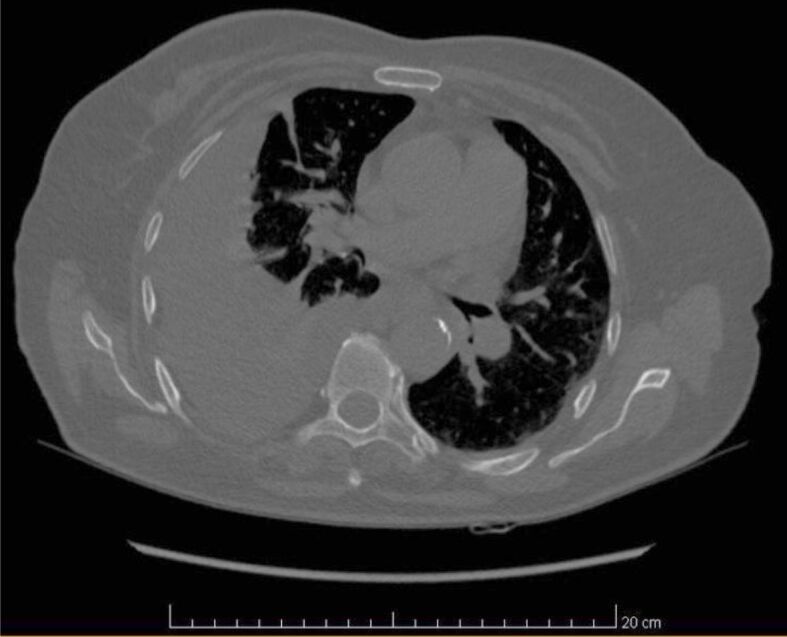

Abstract Image